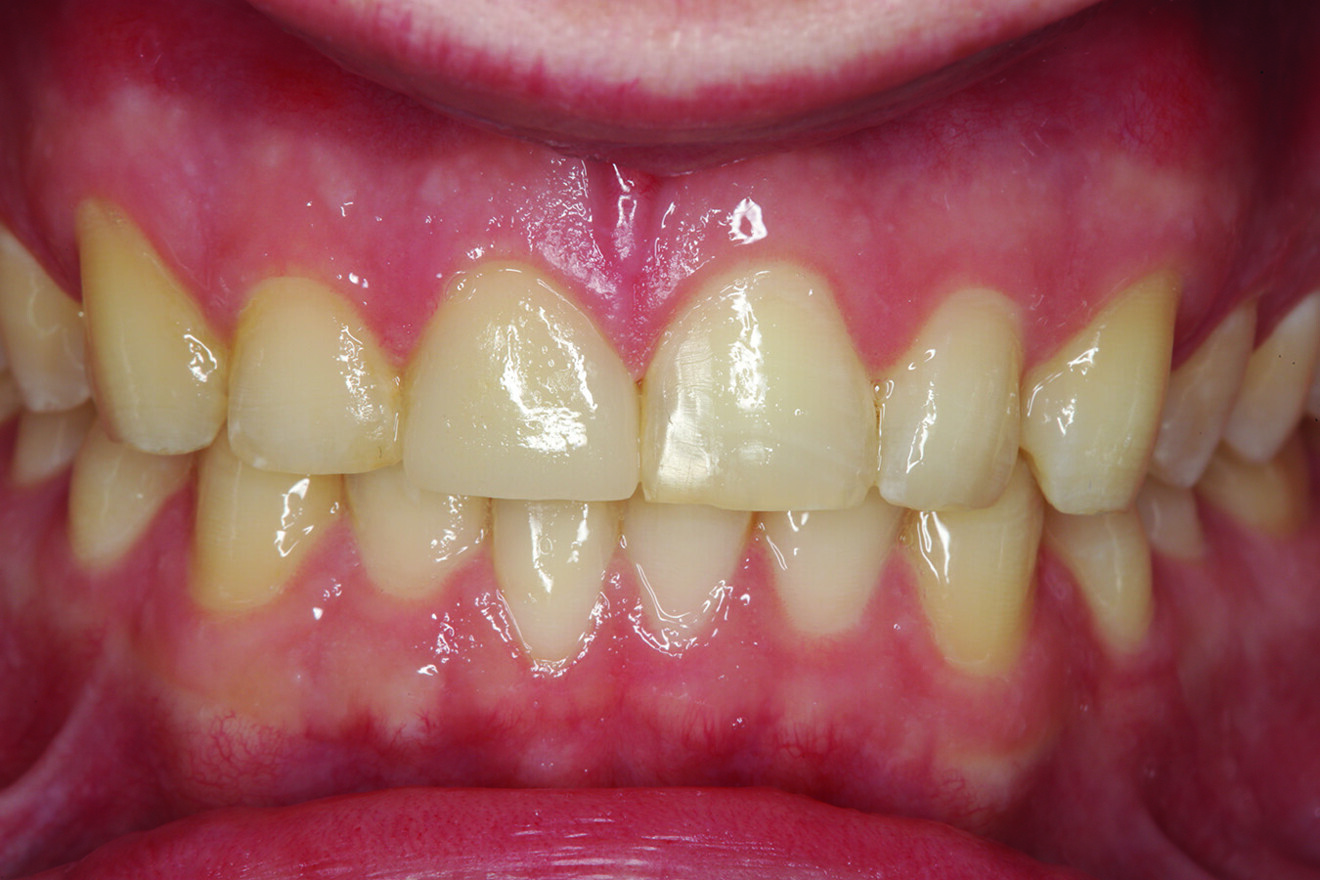

Fig. 17: Six-month post-op retracted facial view of the restored teeth #11 and 41 with the teeth in maximum intercuspation. Aesthetic and functional harmony had been achieved.

Orthodontics to correct tooth alignment was dis­cussed with the patient, but the patient did not desire this option. An alternative treatment plan was to restore tooth #41 in such a way that the position of the tooth facially and its incisal edge would not engage the palatal sur­face of tooth #11 prematurely and then to restore the pal­atal surface and incisal–facial fractured area with ceramic to replace the lost enamel and reinforce the remaining tooth structure. The decision was made to restore tooth #11 with a ceramic crown and tooth #41 with a direct composite restoration. For tooth #11, an aesthetic match to tooth #21 could be bet­ter achieved in layered ceramic. Composite resin was chosen as a more conservative and less costly option for tooth #41, but the patient was told that it may require a ceramic restoration later.